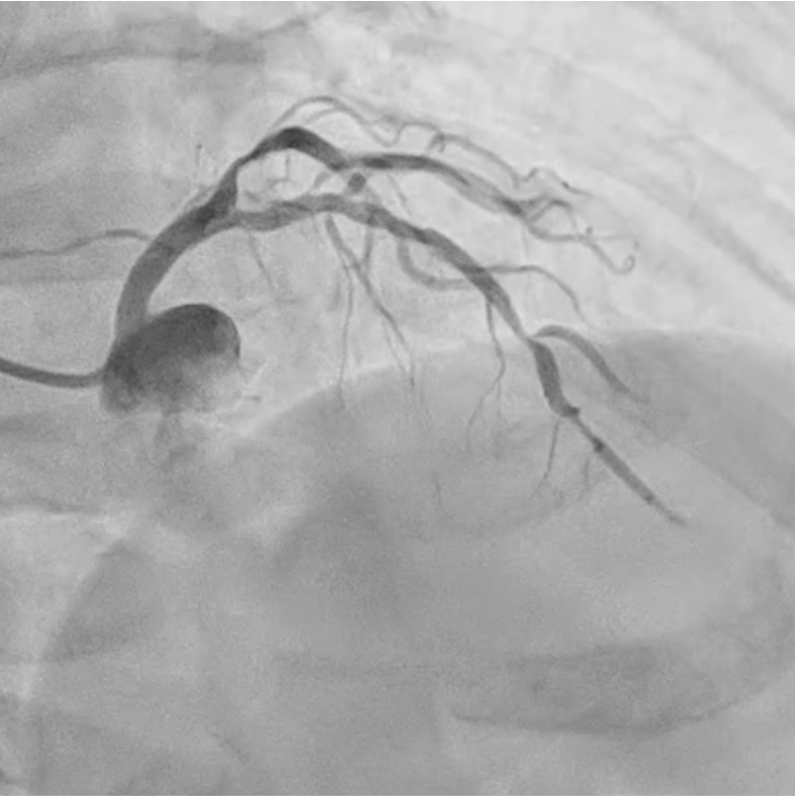

Coronary angiography and optical frequency domain imaging (OFDI) revealed a severe, focal, non-calcified stenosis in the mid-left anterior descending artery (LAD). Left ventricular systolic function was preserved without regional wall motion abnormalities.

A 6 Fr guiding catheter was engaged in the left coronary ostium, and a 0.014-inch guidewire was advanced into the distal LAD. The first diagonal branch (D1) was protected by the jailed balloon technique, and direct stenting was performed. A drug-eluting stent was positioned at the target lesion; however, during balloon inflation, a pinhole rupture occurred in the stent-mounted balloon, resulting in incomplete expansion limited to the proximal segment.